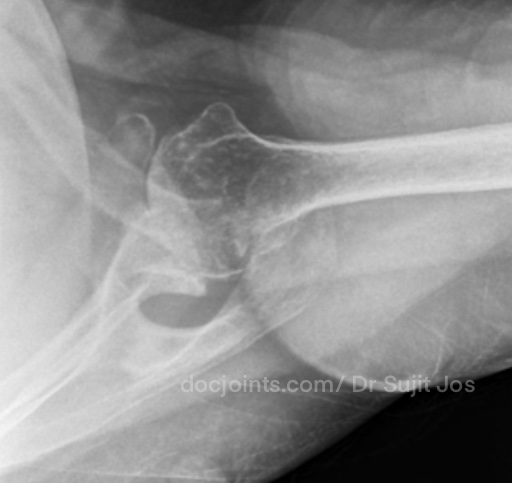

On presentation to the OP, the lifting power of the shoulder was significantly affected on strength testing (emply can test indicating supraspinatus tendon tear) and outward rotation was very weak (indicating Infraspinatus tendon tear). Xray and MRI images attached below.

There was significant fatty infiltration of the rotator cuff muscles along with osteoarthritis of the shoulder joint. Treatment options were discussed. Reverse shoulder arthroplasty is the modern treatment for this type of pathology, which can restore muscle function by orienting the shoulder centre of rotation in such a way that the Deltoid muscle can help in elevating the limb from neutral position (Read more about Reverse shoulder replacement >>).